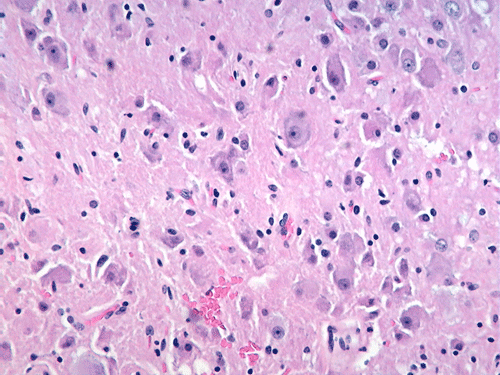

The excised specimen gave the features of cerebellum with greatly expanded cerebellar folia with myelination on the surface of the folia (Panel A, letter S indicates the material used to support the specimen) which can be seen easily on fresh specimen. . The expanded folia are most obvious in fixed specimen (Panel B). On pendicular section of the specimen (Panel C, arrow head points to the pial surface), the normal archicheture of cerebellum is totally effaced. The outer layer is composed of a layer of white matter while the inner half is composed of collections of large, ganglion cells ( in indicates the interface of the two layers which is magnified in Panel D). Multiple calcifications (darks spots in Panel C) are also present.The deeper layers of ganglion cells are composed of large, ganglioinic neurons of similar size and separated by only a small amount of glial tissue (Panel E and F). Multiple calcifications are seen in the more superficial layer of white matter (Panel G). Many calcified blood vessels (Panel H) are also noted in the deeper layers with ganglionic cells. The superficial white matter layer is well myelinated and strongly reactive for neurofilament (Panel I and J, stained by Luxol fast blue- Creysl Violet and immunohistochemistry for neurofilament respectively correspond to the interface indicated by the * in Panel C). The ganglionic cells are stronly reactive for neurofilament protien and synaptophysin (Panel K and L).

Histologically, a layer of myelinated fibers with large diameter myelinated axons is present in the more superficial location of the expanded where the molecular layer is found at the same level in normal cerebellum. The deeper layer where internal granule layer is supposed to be found is replaced by sheets intermediate sized to large dysplastic neurons that resemble Purkinje cells. In high magnification, these areas resemble gangliocytoma. The proportion of the myelinated outer layer and ganglionic inner layer is variable. The normal Purkinje cell layer is not found. Interspersed in between are much smaller neuronal cells with hyperchromatic, small nuclei that resemble hte internal granular layer. This is, therefore, essentially an “inside-out” architecture of the cerebellum with white matter on large ganglionic neuronal layer in the deeper layer. Mitotic figures are exceptional. Ki-67 labeling is 0-2% for the small number of cases that have been studied. The native white matter of the affected folia is atrophic and rarefied. The histologic features are very specific. Immunohistochemistry is not typically required for diagnosis.